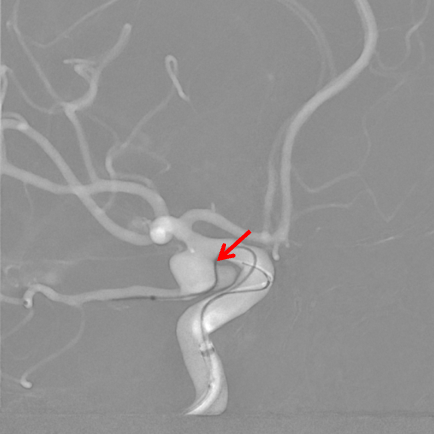

栓塞微导管到位后首先使用弹簧圈栓塞,成篮不稳定,使用Atlas支架4.0mm×21mm保护后交通动脉(箭头所示支架头端及尾端),释放支架的要点在于精准定位,同时判断微导管张力,在预设的释放起点准确打开支架,之后顺行释放支架,支架的尾端打开时须不受颈内动脉管径约束,依靠张力摆动至颈内动脉后交通动脉段远端,起到保护后交通动脉的目的。

术后即刻造影:后交通动脉瘤致密栓塞,后交通动脉及颈内动脉保护良好。